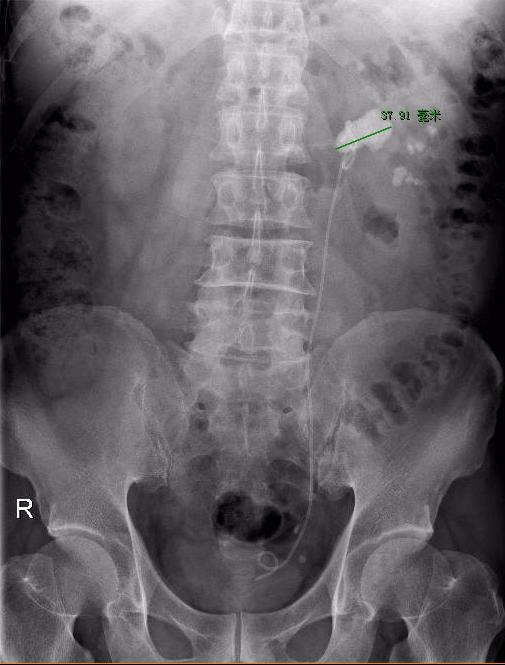

图片2.jpg

CT见左肾结石大并堵塞肾盂口

患者男,58岁,主因“发现肾结石1年余,左侧腰部酸胀2周”就诊。进一步行CT提示:“双肾多发结石,左肾为著,较大结石位于左肾盂开口处,38x36x20mm,左肾轻度积水”;静脉肾盂造影提示:“左肾多发结石、左侧输尿管下段结石并左肾积水;左肾功能差”。予提前2周行左侧输尿管镜下置入输尿管DJ管。现在为进一步行输尿管软镜肾碎石取石术入院。